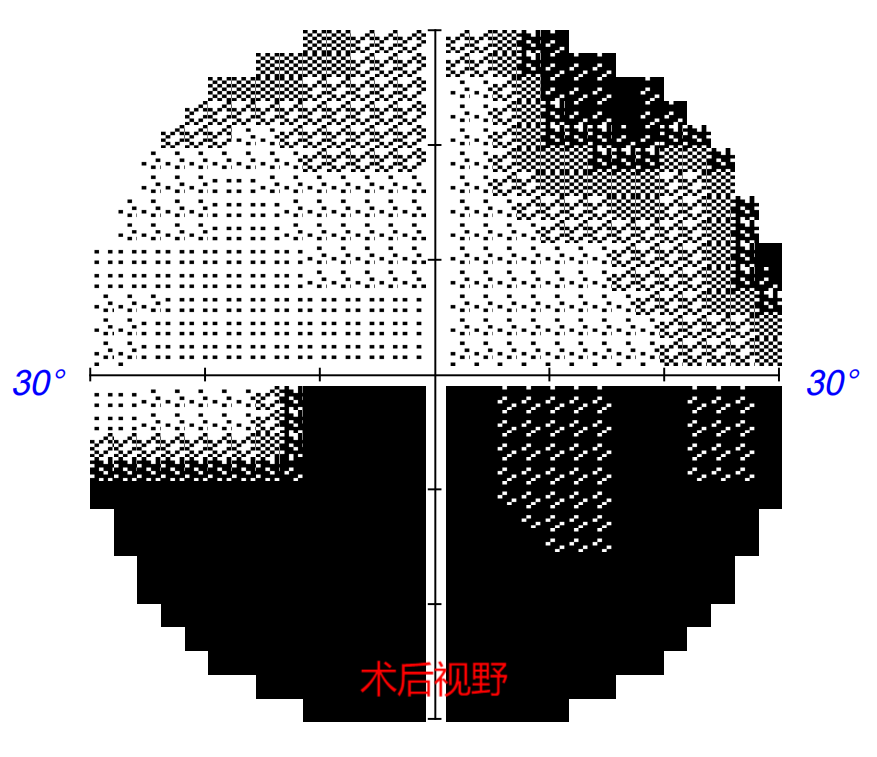

术后1周,张先生的视力恢复至矫正0.5。张先生感慨:就像手机“花屏”修复为清晰流畅的画面。